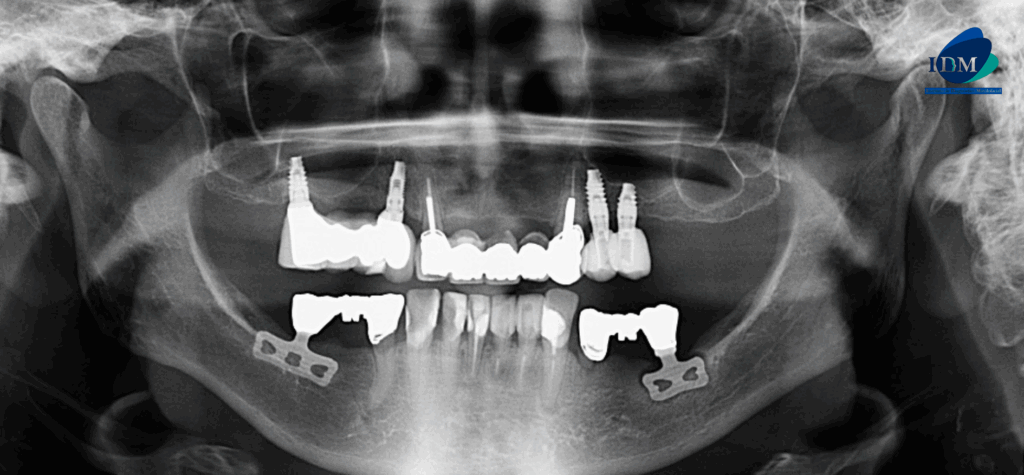

PACIENTE FEMENINO de 81 años acude al Instituto de Diagnóstico Maxilofacial PARA UNA TOMOGRAFÍA para colocación de implantes. A la evaluación de la radiografía panorámica se observa aplanamiento de ambos los contornos condilares, neumatización alveolar de ambos senos maxilares, múltiples piezas con obturación de conductos y coronas protésica, así como la presencia de implantes dentales en el maxilar superior proyectados sobre el piso de seno maxilar, también se observa proceso osteolítico periapical en la pieza 33 y finalmente se observa dos dispositivos metálicos proyectadas en zona de las piezas 36 y 46 compatibles con implantes dentales.

Radiografia Panorámica

Al observar la tomografía computarizada de campo mediano se puede observar que los implantes en el maxilar inferior son efectivamente de tipo laminares o de lámina perforada, además se puede observar en vistas axiales la presencia de una imagen hipodensa circundante al implante de zona de pieza 36 (flecha azul), en vistas transaxiales y tangenciales se evidencian pérdida de continuidad de tejido óseo en tercio cervical; características que no presenta el implante en zona de pieza 46 (flecha amarilla- vista axial). Signos imagenológicos compatible con perimplantitis.